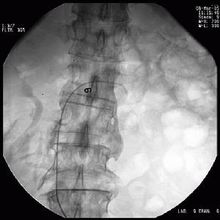

发病前不少患者有呼吸道感染,以后有反复咯血,大多数出现在肾脏病变之前,长者数年(最长可达12年),短者数月,少数则在肾炎后发生。X线检查见两肺有弥漫性或结节状阴影,自肺门向周围扩散,肺尖及近膈肌处清晰,常一侧较重,有的无咯血史,但经痰含铁血黄素及胸片检查证实有出血。在咯血时肺弥散功能减退,出现低氧血症,贫血常见。